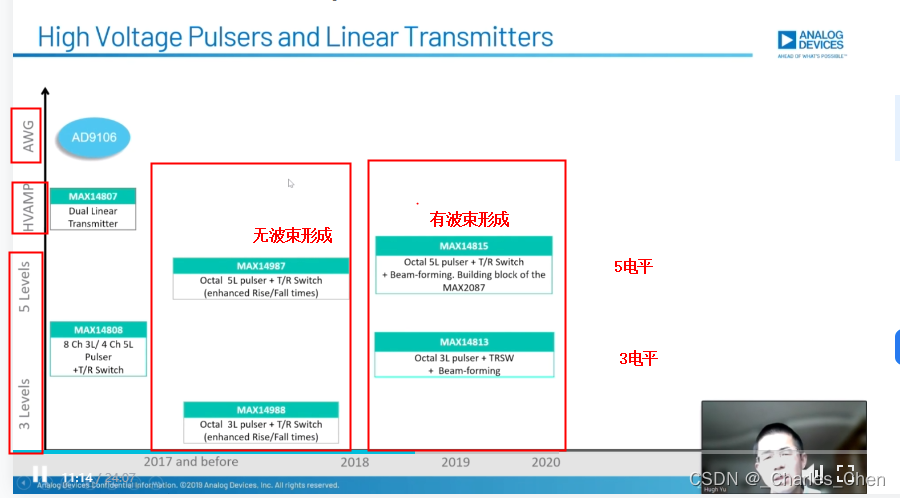

数字发射波束成形器用于产生所要求的数字发射信号,以正确的时间和相位生成聚焦发射信号。高性能超声系统可通过任意波形发生器产生复杂的发射波形,从而优化图像质量。这些情况下,发射波束成形器以大约40MHz速率生成8位至10位数字字符,并以此产生所要求的发射波形。数/模转换器(DAC)将数字波形转换成模拟信号,通过线性高压放大器进行放大,用于驱动传感器单元。由于这种发射技术占用较大体积,而且价格昂贵、需要消耗较高能量,所以,这种架构只限于昂贵的非便携设备。多数超声系统并不使用这种发射波束成形技术,而是采用多级高压脉冲发生器产生需要发射的信号。在这种替代方案中,利用高集成度、高压脉冲发生器快速切换传感器单元至适当的可编程高压电源,产生发射波形。为了产生一个简单的两极发射波形,脉冲发生器需要交替地将传感器单元切换到由数字波束成形器控制的正、负发射电压。更复杂的设计可以让传感器单元切换至多路电源和地,从而产生更复杂、性能更好的多重波形。

近几年,随着二次谐波成像的广泛应用,高压脉冲发生器对于斜率和对称性的要求越来越高。二次谐波成像利用了人体的非线性声学特性。这些非线性特性倾向于将频率fo的声能转变成2fo频率。多种原因使得接收二次谐波信号能够获得更高的图像质量,因此,二次谐波成像得到了广泛应用。

二次谐波成像有两种基本的实现方法。一种称为标准谐波成像,尽可能抑制发射信号的二次谐波,从而使接收到的二次谐波主要源于人体的非线性。这种模式要求二次谐波的发射能量至少低于基波能量50dB。所以,发射脉冲的占空比要求是准确的50%且误差小于±0.2%。另一种方法称为脉冲反相,利用反相后的发射脉冲产生同一图像路径的相位相反的两路接收信号。在接收器中对这两路反相接收信号求和,恢复由于人体非线性产生的谐波信号。这种脉冲反相的方法必须在叠加时尽可能抵消发射脉冲的反相成分。所以,高压脉冲发生器的上升时间和下降时间必须严格一致。